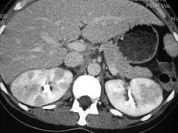

- 单项选择题如图所示,根据这两个时相分析, 最可能的诊断是 ( )

A、肾淋巴瘤

B、急性肾盂肾炎

C、肾梗死

D、肾癌

E、肾囊肿